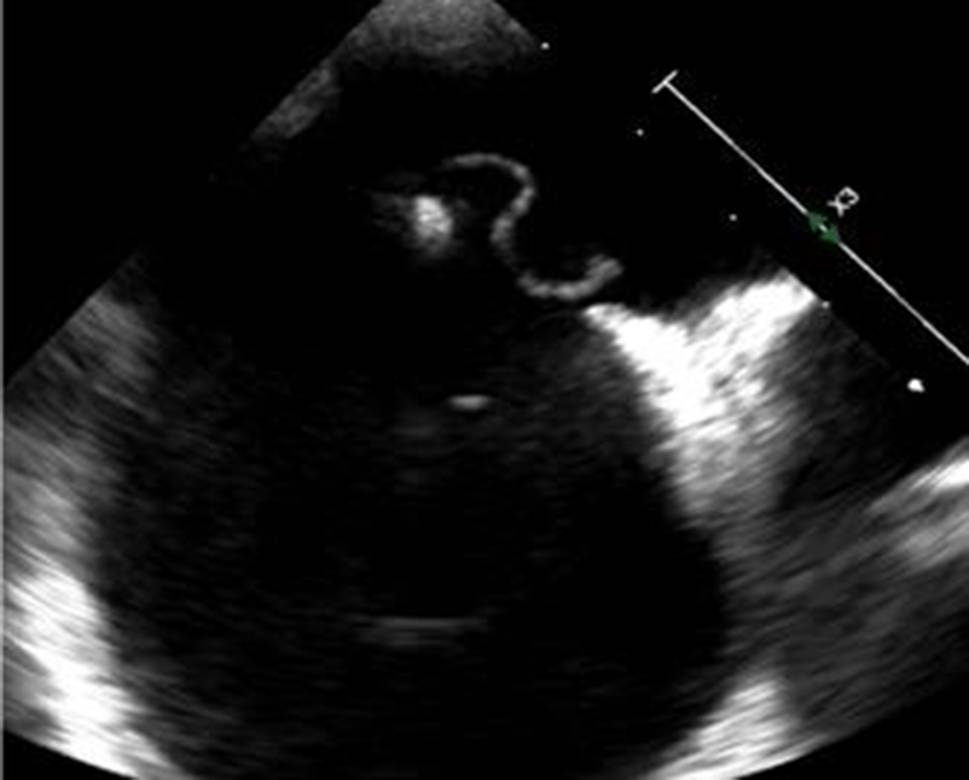

The results of TEE imaging were also recorded to further assess the PFO characteristics. Anatomical PFO characteristics were measured with standard TEE imaging (Epiq, Philips, Best, the Netherlands, and Vivid E95, GE Healthcare, Horten, Norway). The PFO size was measured with two-dimensional TEE before PFO intervention as an “unstretched diameter” in 114 patients (Fig. 2) or with three-dimensional TEE during PFO intervention, after placement of a guidewire through the PFO, resulting in a maximal “stretched diameter” in 109 patients (Fig. 3). Atrial septal excursion was measured on an image with the best cross section of the atrial septum between 30 to 60 degrees (Fig. 2).

Fig. 2

TTE image of an unstretched PFO